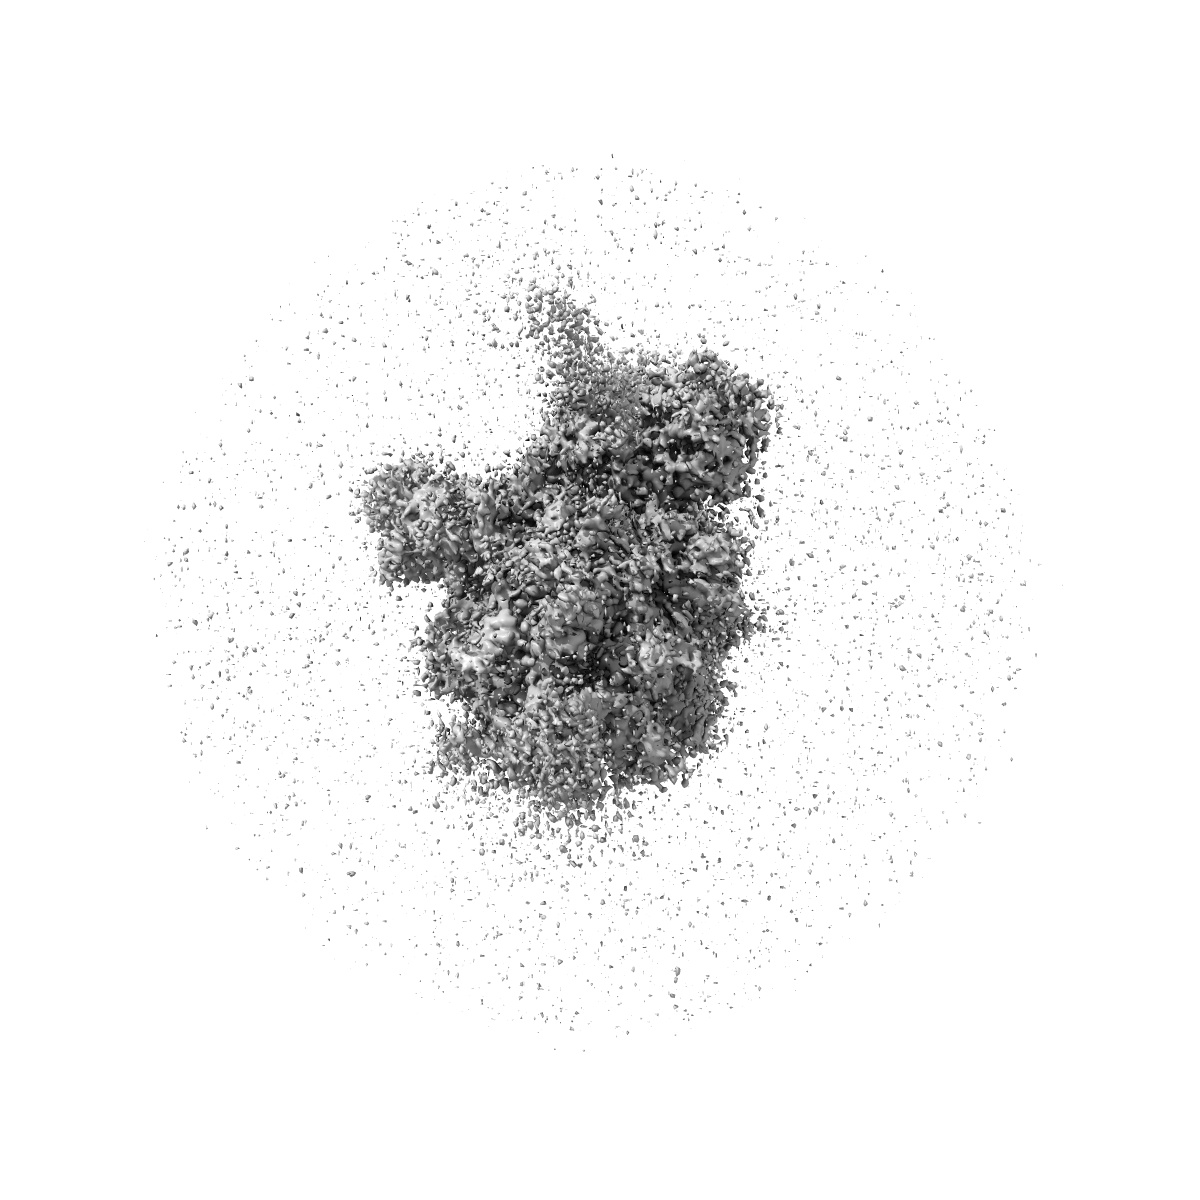

S protein of Delta variant in complex with ZWC6

Sample: S protein of Delta variant in complex with ZWC6